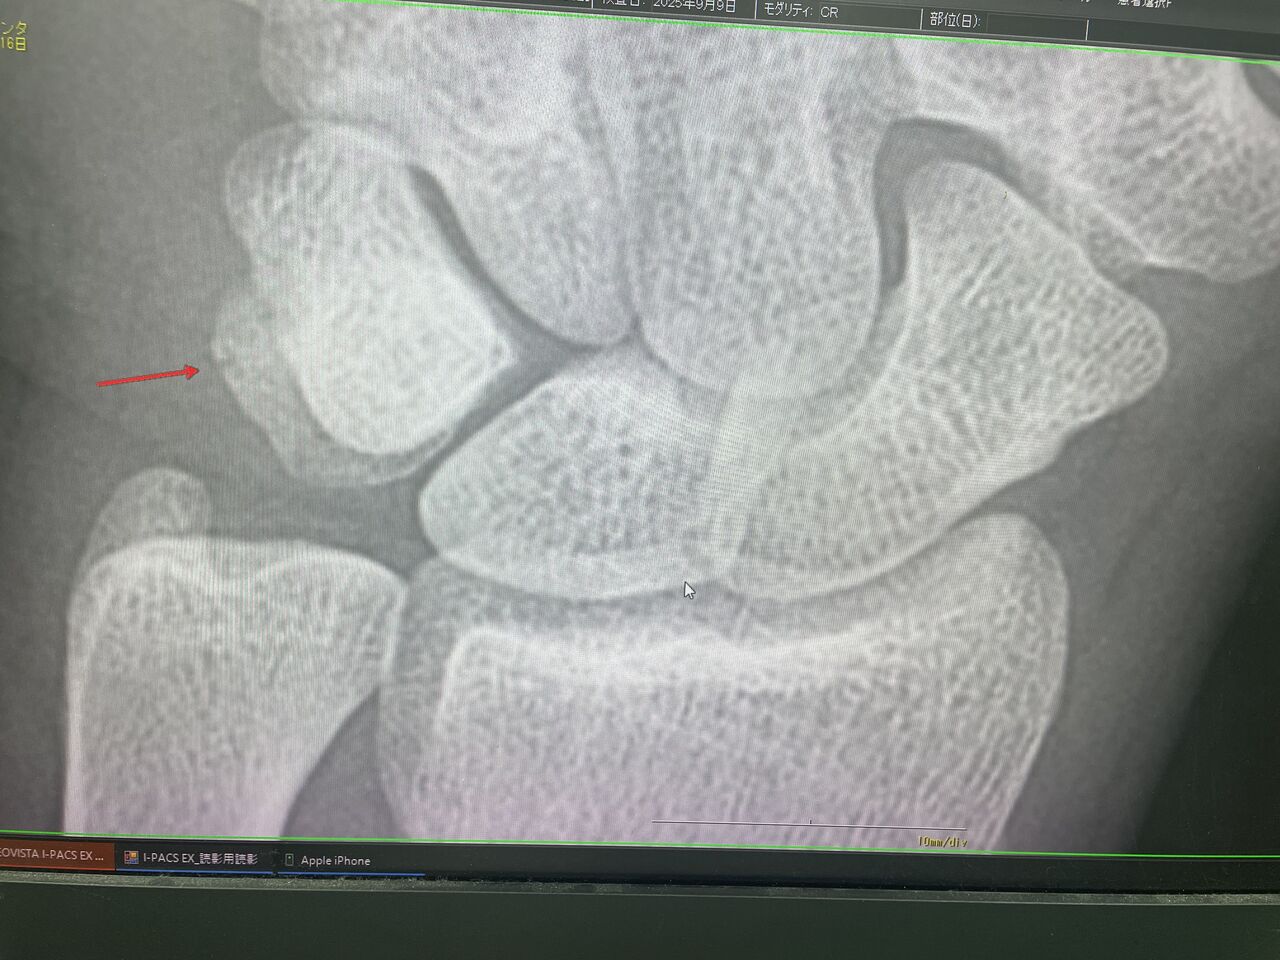

チームドクターしている

鷺ノ宮製作所 都市対抗出場

大会前に、手首にヒビが入るも、テーピングを使って

ヒットの放って 8強まで、進みました

今回は残念でしたが、次は日本選手権で優勝を

狙っていきます